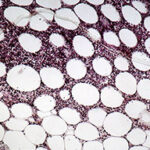

Histopathology. The histopathologic appearance itself is not sufficiently specific to exclude other diseases . The classical description of the disease is that it evolves through three stages. In the first phase, there is only erythema and induration clinically. Histologically, acute inflammation is found in the fat lobules with degeneration of fat cells and an infiltrate of neutrophils, lymphocytes, and macrophages. The second phase has an infiltrate discretely localized to the fat lobules, consisting mainly of macrophages, foam cells, and extracellular lipid droplets. In some cases, the lesions perforate the skin surface and discharge a sterile, oily liquid. The third phase |

has depressed and indurated clinical lesions. Fibroblasts, collagen, and scattered lymphocytes and a few plasma cells replace the fat. Vascular changes are mild . |